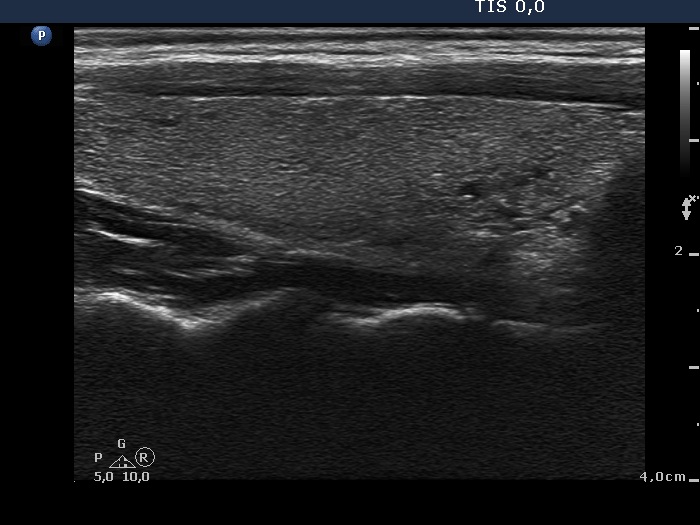

Metastasis of a kidney carcinoma to the thyroid - case 1574 |

Benign hyperplastic nodule (histological diagnosis) - case 1582 |

Both images show one relatively large granule which correspond to punctate echogenic foci.

Parts of the hyperechogenic granules are located in cystic area, while others are found in the solid part of the lesion. The latter might be punctate echogenic foci.